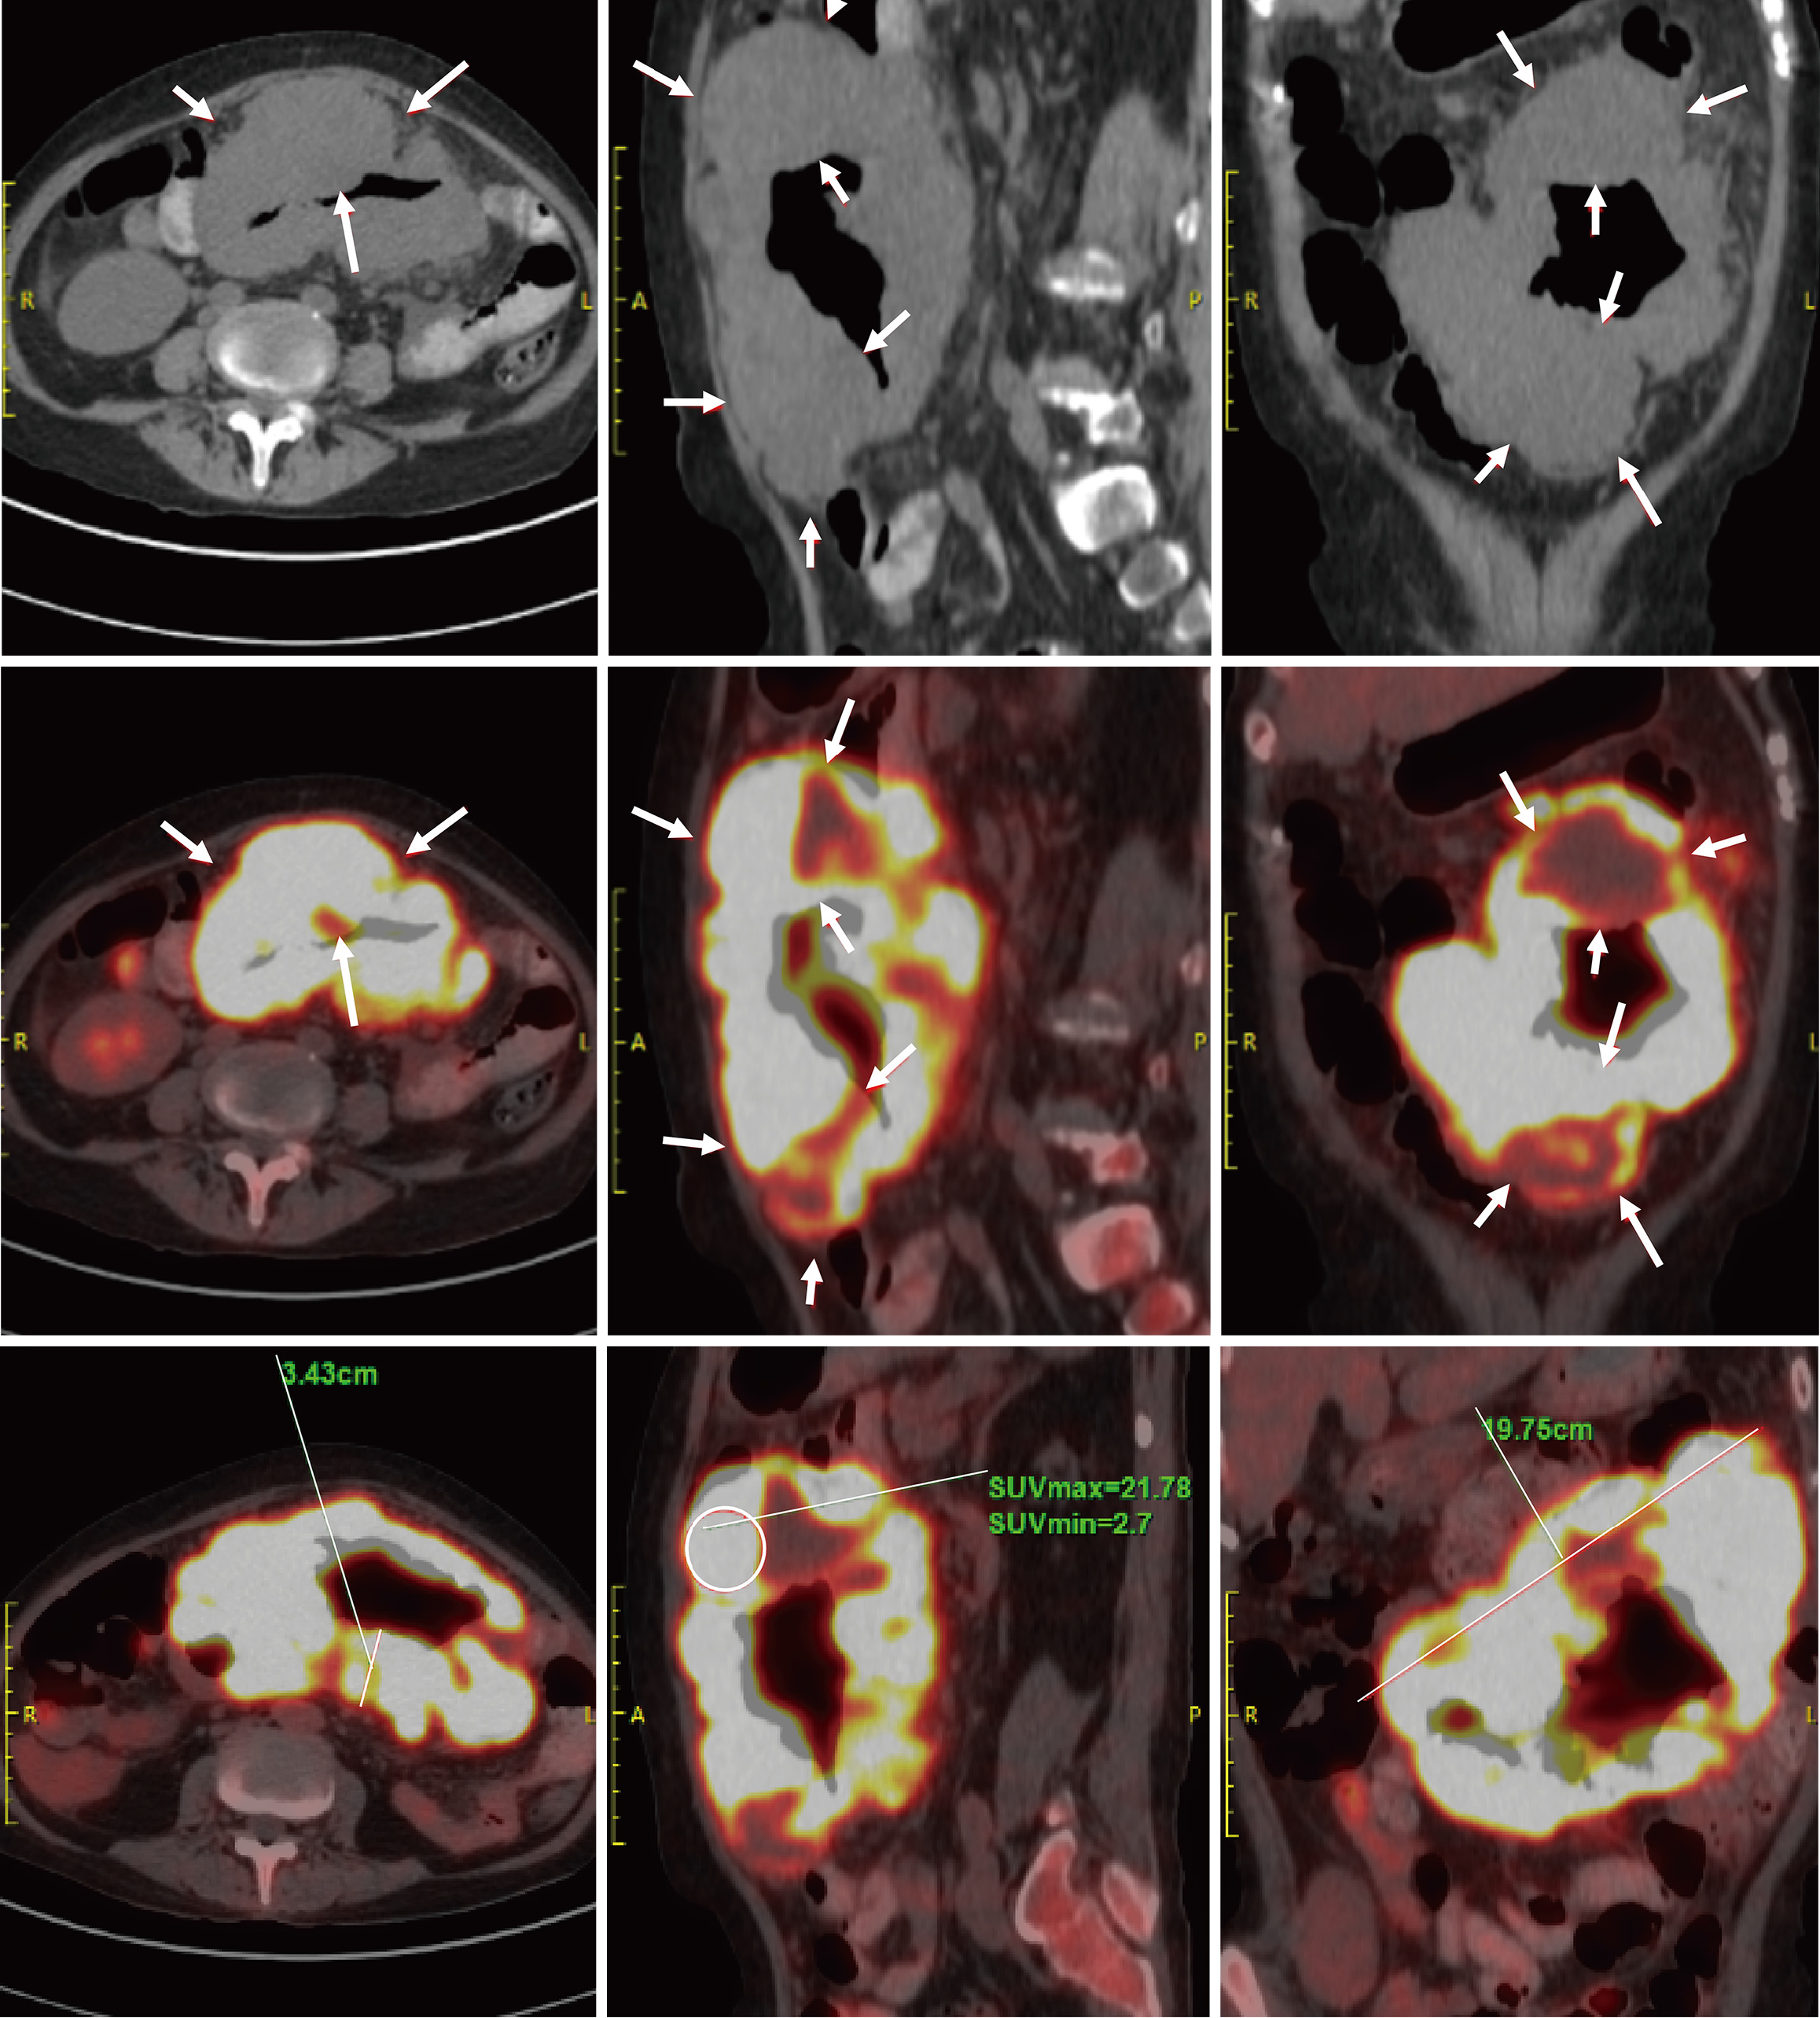

Figure 2 Positron emission tomography/computed tomography findings.

Segmental circumferential thickening and mass formation were noted in the second segment of the small intestine, extending from the left upper to mid-abdomen, with significantly increased fluorodeoxyglucose uptake. Multiple enlarged lymph nodes were observed in the abdominal cavity surrounding the small intestinal lesion, also demonstrating markedly elevated fluorodeoxyglucose uptake. Arrow: Segmental small bowel wall thickening and a mass, respectively. The circled areas highlight regions with increased fluorodeoxyglucose uptake. The solid lines mark the measured lengths.